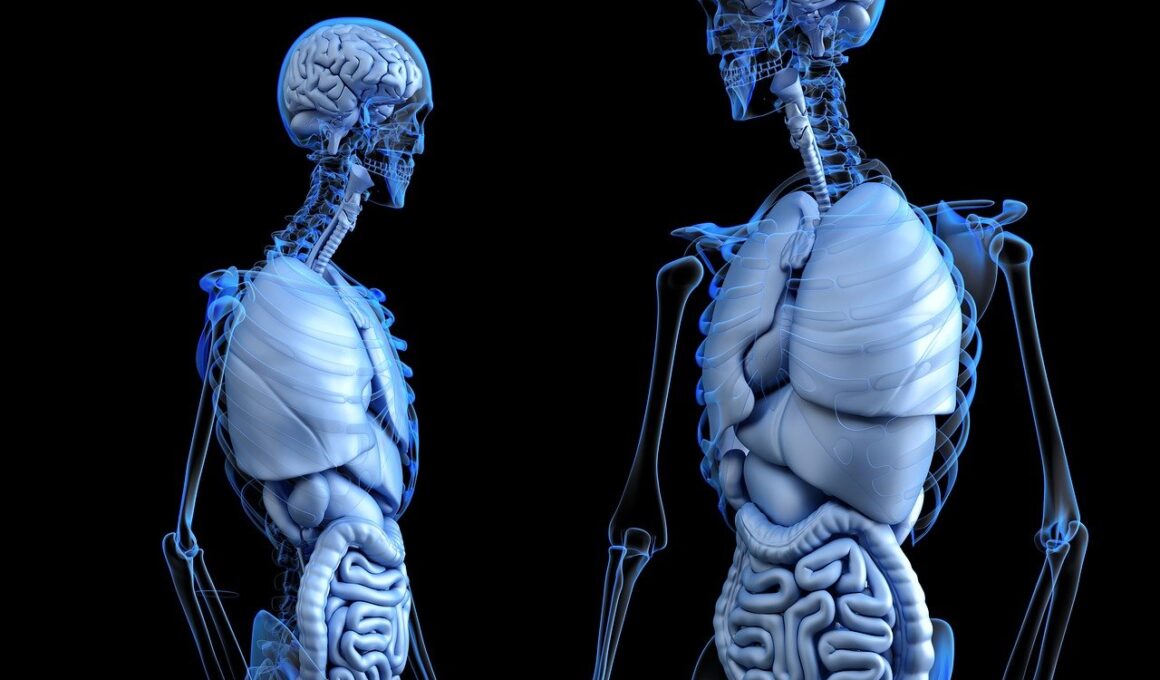

Gut health plays a crucial role in overall brain function, particularly in conditions like attention deficit disorders (ADHD). The gut-brain axis is a complex communication network linking the gastrointestinal tract and the brain. This connection signifies that the health of the gut microbiome can directly influence behavior and cognitive functions. Research suggests that imbalances in gut bacteria may exacerbate ADHD symptoms. Healthy gut flora can produce neurotransmitters such as serotonin and dopamine, which are essential for mood regulation and focus. Foods rich in probiotics, like yogurt and fermented vegetables, can help maintain a balanced gut microbiome. A healthy gut environment is vital for neurological development, especially during childhood, when ADHD is often diagnosed. Moreover, gut inflammation has been linked to neuroinflammation, which may further impact attention and learning capabilities. By nourishing the gut with fiber-rich foods and avoiding processed sugars, we can create an optimal environment for brain health. Promoting gut health encompasses holistic dietary changes that can alter not only our digestive health but also our mental clarity and attention spans, ultimately benefiting those with ADHD.

In conclusion, the intricate relationship between gut health and brain function opens up various avenues for addressing attention deficit disorders. By fostering a well-balanced gut microbiome through proper nutrition, lifestyle modifications, and supplementation where necessary, individuals can potentially alleviate symptoms and enhance cognitive functions. Parents and caregivers should take proactive steps to identify dietary patterns that contribute negatively to gut health. Furthermore, understanding the significance of nutrition in children’s development is essential. Collaboration with healthcare providers can guide families in adopting evidence-based approaches tailored to their unique circumstances. The focus on whole, unprocessed foods rich in fibers, omega-3 fatty acids, and probiotics can lay the foundation for a healthier gut and brain. Additionally, promoting mental wellness through adequate physical activity and relaxation practices supports overall development. In managing attention deficit disorders, a multifaceted approach incorporating gut health, nutrition, and lifestyle can provide the most beneficial outcomes. Therefore, a comprehensive understanding of gut health is vital not only for mitigating ADHD symptoms but also for fostering optimal brain function among individuals across all ages.